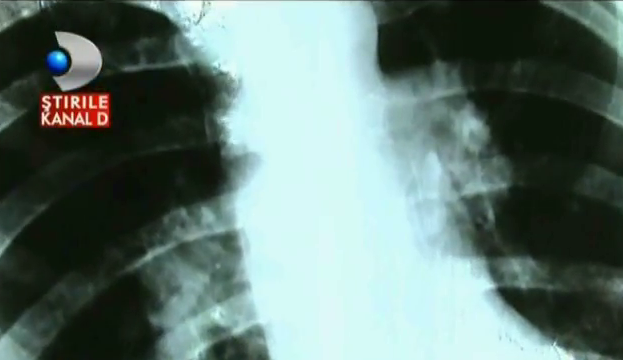

Viata Violetei s-a schimbat radical din cauza anticonceptionalelor. Femeia a fost diagnosticata cu embolism pulmonar.

Plamanii ei sunt plini cu trombe si cheaguri de sange din cauza anticonceptionalelor. Doar pozele de la nunta ii mai amintest Violetei de femeia care era odata. mama a doi copii se lupta sa-si recapete sanatatea dupa o greseala pe care medicii ieseni i-au semnalat-o acum.

Luna de luna, timp de 12 ani, femeia a luat pilule anticonceptionale prescrise de medic, fara sa mai mearga la consult sau analize, pana intr-o zi cand a lesinat. Speriata femeia a mers la doctor, iar diagnosticul a fost unul teribil: embolism pulmonar.